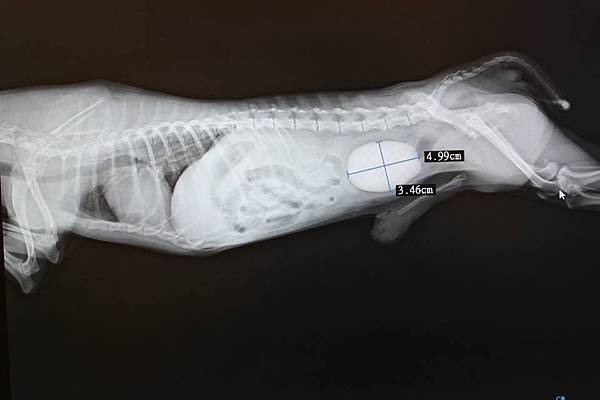

這個嚴重膀胱結石的小朋友

在來就診前持續出現排尿困難 嘔吐 血尿的情形

經X光與超音波確診後

發現他小小的身軀裡面竟然出現如此巨大的膀胱結石

緊急安排手術取出